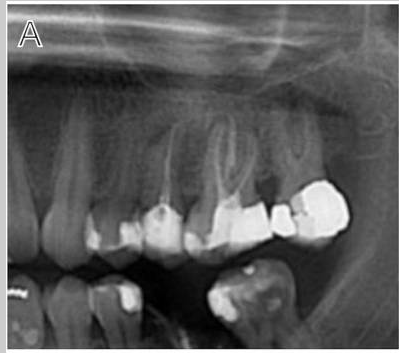

Case photos below provided by Rehberger Bescós F, Salgado Peralvo ÁO, Chamorro Petronacci CM, Chele D, Camacho Alonso F, Peñarrocha Oltra D, Lado Baleato Ó, Pérez Sayáns M. [Marginal bone loss and associated factors in immediate dental implants: a retrospective clinical study.](Marginal bone loss and associated factors in immediate dental implants: a retrospective clinical study - PMC)

Measurements for the calculation of the MBL performed: A Preoperative evaluation; B immediate postoperative period; C 2 months after placement of the implants; D 36 month follow-up

This study concluded:

The present study supports the clinical efficacy of immediate implant placement protocol with high survival rates and acceptable MBL. Regarding the latter, the insertion of implants bone level about 3 mm infracrestal should be considered to ensure a subcrestal implant platform position during bone remodeling during the first months after implantation. The insertion of immediate implants in the jaw compared to the maxilla, the abutment height and rotational abutments demonstrated a positive impact over the MBL.